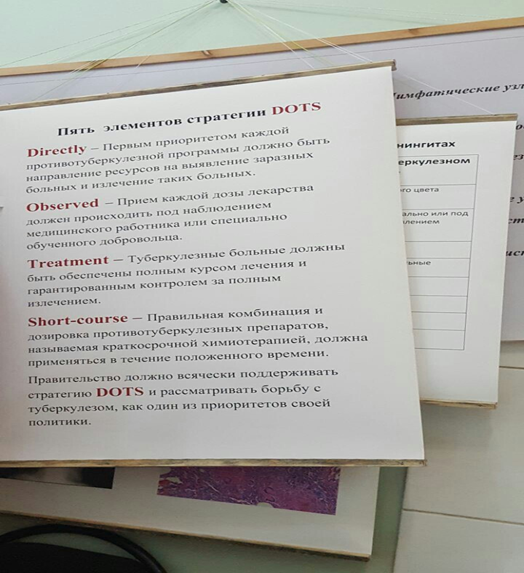

Лечение туберкулеза: Методики химиотерапии

Раздел: Визуальный дайджест